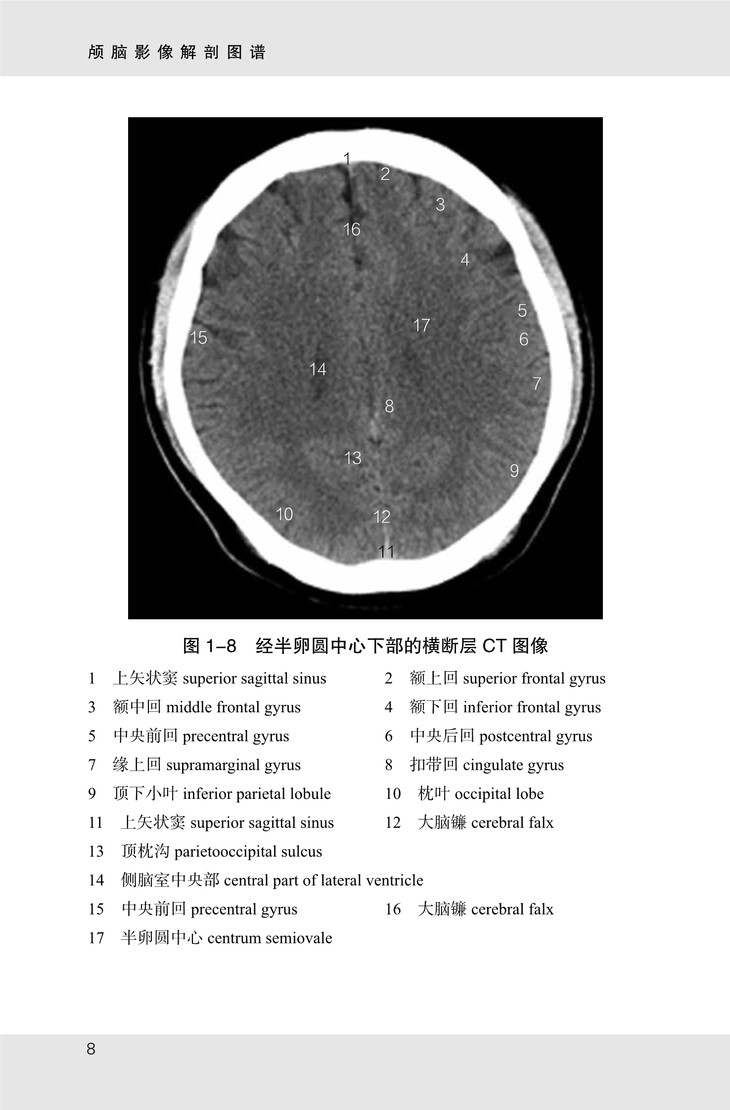

《颅脑影像解剖图谱》共有图像 175 幅,包括以下四个部分:

(1)颅脑 CT 图像,从颅顶至枕骨大孔共有横断层图像 21 幅,扫描基线为眦耳线;